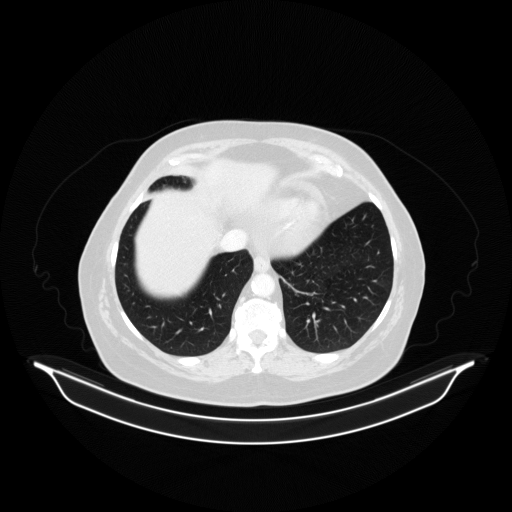

Image Grid

4Γ—3 grid: Rows show different image types (Original NATIVE, Reconstructed NATIVE, Original VENOUS, Generated VENOUS), Columns show windowing techniques (No Window, Lung Window, Mediastinum Window)

Original VENOUS CT scan

Lung window (WL -600, WW 1500 β†’ Low βˆ’1350, High +150)

Generated VENOUS CT scan (A→B translation)